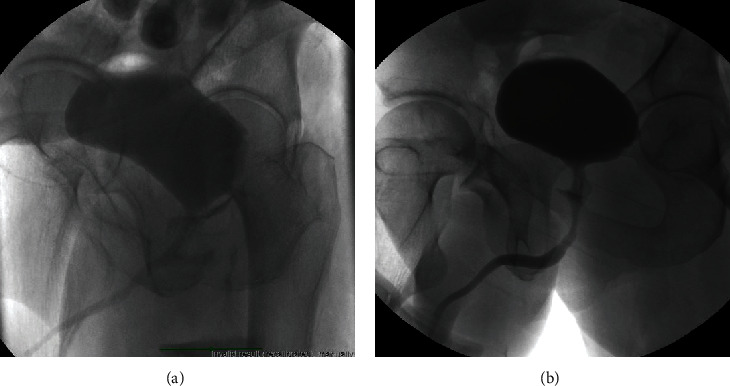

Penetrating posterior urethral trauma from gunshot wounds (GSW) is rare and requires prompt treatment to minimize complications. Data regarding the management of such cases is scarce in the literature and poorly addressed in the guidelines. Different management approaches exist, including urinary diversion with immediate versus delayed urethroplasty/fistula repair. We present our case series to add to our experience to the literature. Three patients aged 18-44 presented with ballistic posterior urethra injuries from GSW. Initial management involved urethral catheter placement, with one patient requiring operative placement of urethral and suprapubic catheters (SPTs). Complications included recurrent membranous stricture, urinary retention, rectourethral fistula, and erectile dysfunction (ED). Posterior urethral injuries from GSW are complex as they can be either isolated or affect adjacent organs. Bladder, ureteral, and urethral injuries must be ruled out. Unlike bladder neck injuries, immediate urethroplasty/fistula repair would be very challenging and not advised for standard prostatic or membranous injuries. Urethral catheter or suprapubic tube is recommended and can result in fistula closure and urethral patency. It is critical to maintain close follow-up with the patient due to the possibility of stricture recurrence. Urethroplasty in a delayed fashion can be very successful.